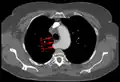

Arteria subclavia aberrante mediante TAC. (1) Tráquea, (2) Esófago, (3) Arteria subclavia aberrante

Arteria subclavia aberrante mediante TAC. (1) Tráquea, (2) Esófago, (3) Arteria subclavia aberrante -